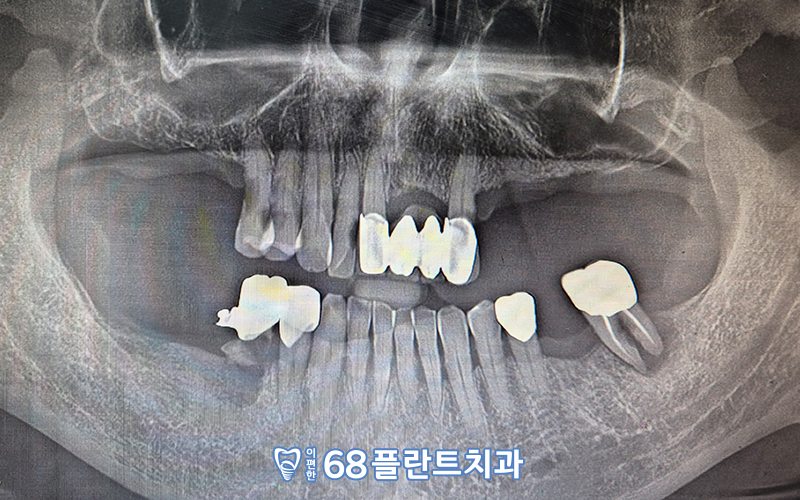

오늘 소개해드릴 분께서는

어금니 부위가 거의 대부분 상실된 상태로,

저작하는데에 많은 불편감을 느끼고 계셨습니다.

정밀한 체크를 위해 파노라마를 촬영해보니,

남아있는 치아들도

흔들리는 치아 혹은

예후가 좋지 않은 치아가

다수 관찰되었는데요.

살리기 어려운 치아들은 발치를 진행하고,

상실된 부위와 더불어

임플란트 치료를 진행하기로 하였습니다.